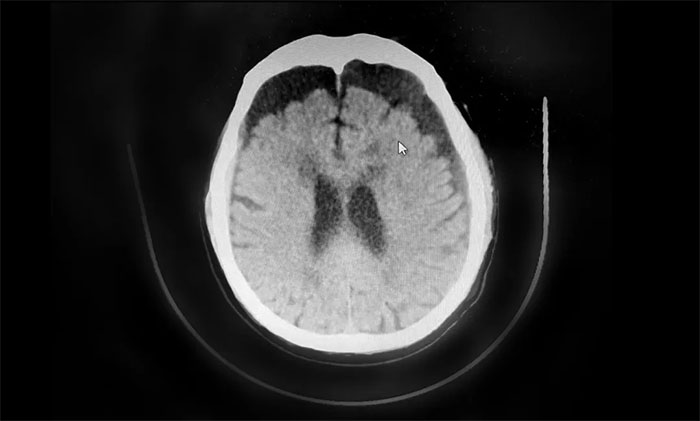

行顱腦CT檢查,患者雙側(cè)額顳枕頂部可見硬膜下積液血腫,雙側(cè)額葉受壓明顯,不排除積液血腫進一步加重。若不及時手術(shù)治療,病情可能進一步惡化,甚至可能危及生命。

▲ 患者雙側(cè)額頂部硬膜下積液血腫明顯